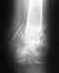

Вопрос о "нормальности отека", мягко говоря, наивен. Результат лечения определяется качеством восстановления формы и соотношений элементов голеностопного сустава. Величина отека ничего не говорит об этом, отек может быть любой (и сильно выраженный, и слабо) как при плохом, так и при удовлетворительном положении отломков. Так что надо смотреть рентгенограммы.